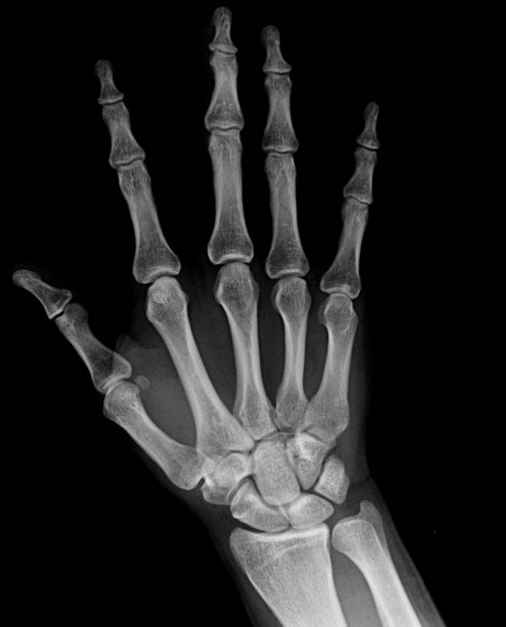

灰度的概念晦涩难懂,但是它的应用在生活中却不鲜见,在医学、图像识别领域有很广泛的用途。比如我们在医院体检时拍摄的CT(电子计算机断层扫描)、MR(磁共振检查)、B超、X光都是灰度图像,以灰阶即亮度模式的形式来诊断病症。

此外,基于物体的边缘呈现灰度的不连续性的原理还可以进行图像分割,常用于生物医学图像的分析,用于测量人体器官、组织或病灶的体积,用于医学图像的3D重建,例如两个彗星细胞粘连的情况,提出一种基于区域灰度值的路径探测方法.对粘连细胞进行分割,便于可视化,可取得较理想的分割效果。另外,也可以用灰度值实现显微图像的细胞计数判读。